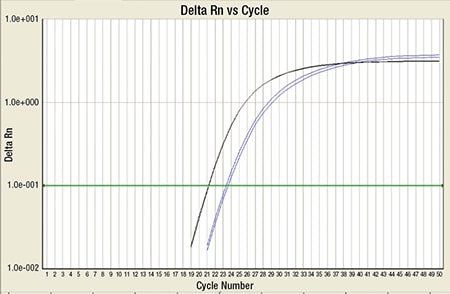

A bone marrow biopsy was then performed and revealed a hypercellular marrow with left shifted maturation in the myeloid lineage with 77 percent blasts (Fig. 6). Blast morphology was similar to the peripheral blood. Flow cytometry performed on the bone marrow was identical to the peripheral blood. Conventional karyotype performed on the bone marrow revealed a normal male chromosome complement with no abnormalities identified. Due to the clinical suspicion of APL along with blast morphology and immunophenotype, despite negative FISH and karyotype, reverse transcription-polymerase chain reaction (RT-PCR) testing was obtained.7 Testing revealed a cryptic t(15;17) with the bcr-3 transcript, and the patient was formally diagnosed with APL (Fig. 7). Despite starting ATRA, the patient developed DIC, which was effectively treated with transfusion. The patient was discharged home one month later and remains in remission more than three years later.